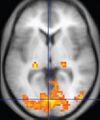

| Functional MRI (fMRI) |

Blood-oxygen-level dependent imaging |

BOLD |

Changes in oxygen saturation-dependent magnetism of hemoglobin reflects tissue activity.[87]

|

Localizing highly active brain areas before surgery, also used in research of cognition.[88]